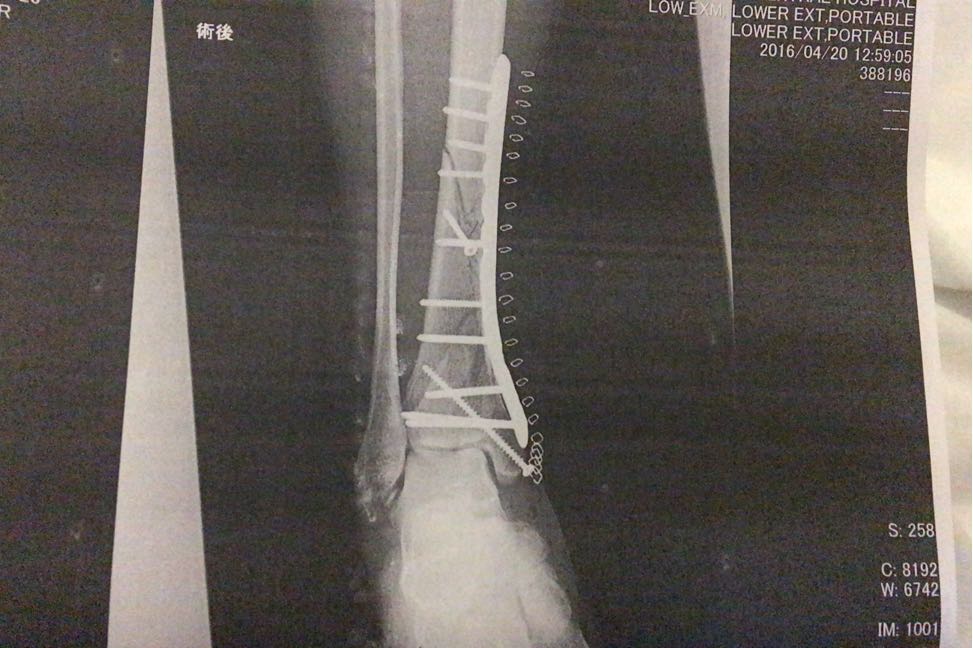

ちなみに、右足の手術はこんな感じだったらしいです。

プレートがSIDIのブーツみたいでカッコ良いですね♪( ´▽`)

随分綺麗に整復されてますね。腕の良いDrで良かったですね。

Tomo46くん

やっぱり本業の人から見ると、違いが分かるもんなんだね…。

手術の予定時間より倍近く掛かって、元の位置と近いところに戻してもらえたので、あとは骨同士がくっついたら言うことなしだな、と♪